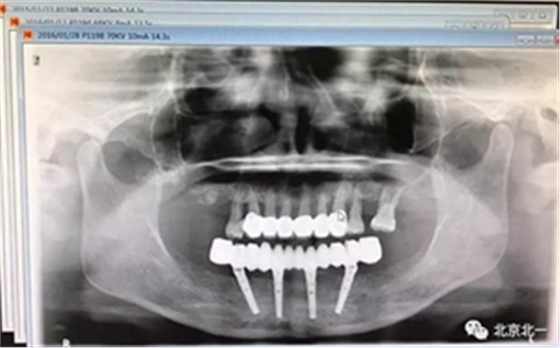

圖二十二:2015年到2016年復(fù)查時X片 ,有圖有真相

沒有假貨,貨真價實,完成三年復(fù)查。